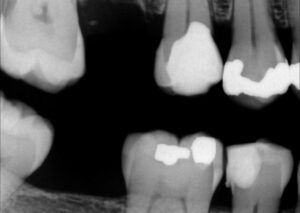

Extreme DME case using the Rhondium DME wedge in sequence with the Garrison Compositight system with a supercomposite placed incrementally to support what little is left of this extremely-compromised second bicuspid.

#VocoGrandioSO #RhondiumDME #GarrisonCompositight